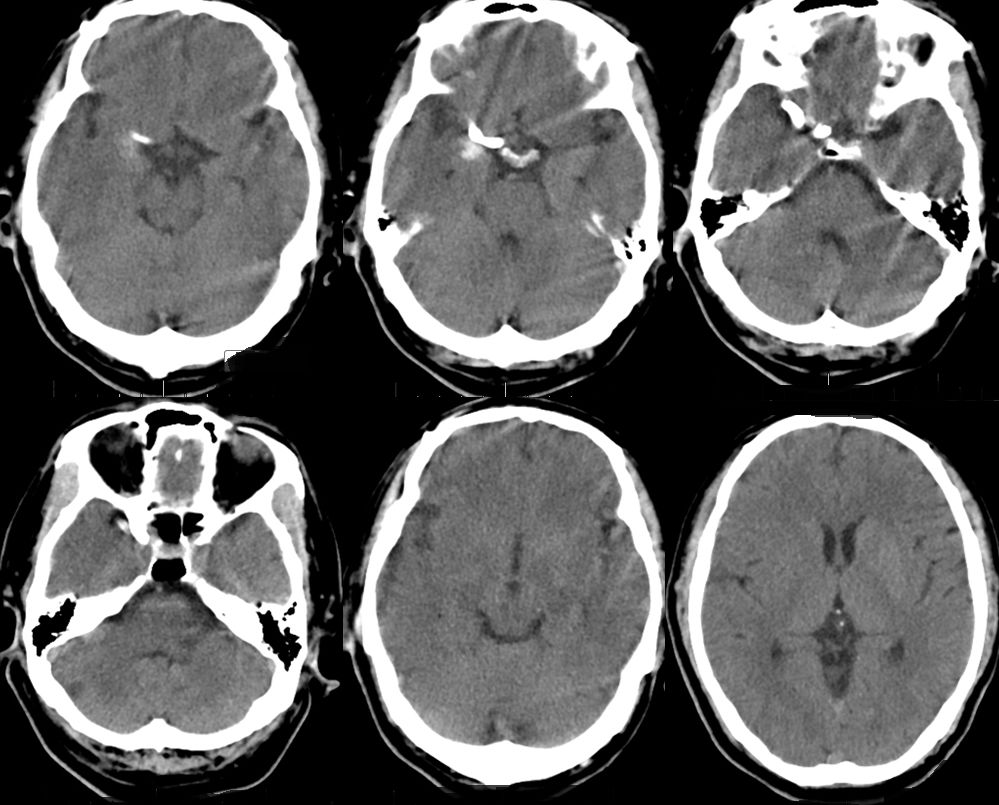

1、术后18小时CT(图五)。

图五

术后3天CT(图八)。

图八

术前讨论:如何使患者获得最大受益?因为是夹层动脉瘤,如果填圈治疗,一是外侧豆纹动脉会即刻闭塞,更易引起临床症状;二是填圈治疗有使夹层动脉瘤撕开、出血的风险。所以经讨论我们决定采取一种折中方案,只放密网支架而不填圈的手术方式。我们希望通过密网支架的支撑,使夹层动脉瘤慢慢消失。通过慢性闭塞,给夹层动脉瘤上方的豆纹动脉部位一个代偿血管增生的时间,减少患者发生偏瘫的概率。经过精准测量后,选择合适支架。术中手术顺利,术后进行血管三维重建,密网支架放置良好,贴壁良好,可以清晰的看到豆纹动脉。术后患者回到病房后,一般情况良好。术后18小时后患者出现言语含糊、左侧中枢性面舌瘫,左侧肢体偏瘫,CT排查出血后考虑是患者夹层动脉瘤上方的豆纹动脉闭塞引起的症状。立即行全脑血管造影,发现豆纹动脉确实消失。确定豆纹动脉消失是引起患者临床症状的一个主要原因。这是天坛医院第一例在密网支架植入术后第一天就复查造影的患者。造影结果让我们惊喜的发现,密网支架治疗后,不到18个小时,患者的动脉瘤几乎完全消失。从而证明,我们的手术通过精准测量,选择合适的密网支架对夹层动脉瘤的治疗效果以及夹层的修复效果是非常明显的。当然,患者出现穿支动脉的闭塞,是我们术前充分考虑的,且无法避免的一个并发症。术后给予神经康复,高压氧治疗,患者有明显的好转趋势。我们希望通过后续的康复治疗可以使患者的生活接近正常,同时我们也在密切随访患者,希望患者动脉瘤完全消失,并且正常生活。